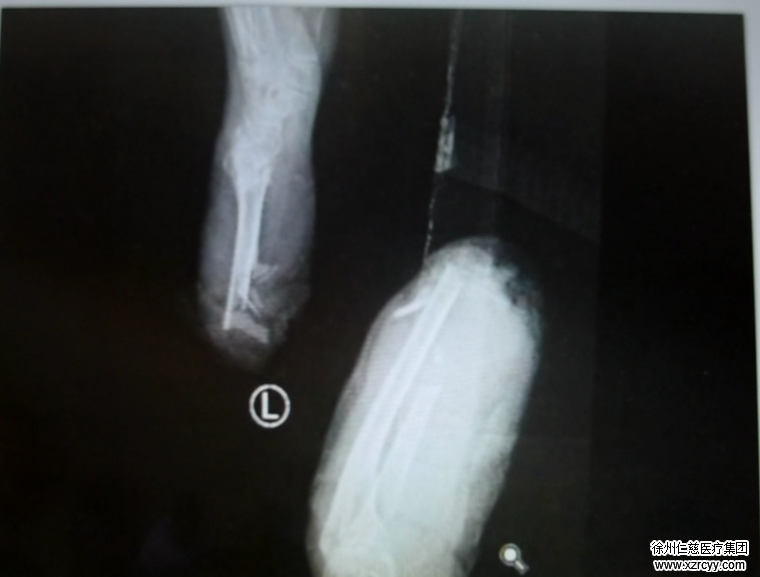

马师傅看见这情景吓坏了,他一边喊,一边赶紧跳下拖拉机用手里的木撬去挡风扇,可情况太危急,短短的几秒,左老太的左臂就已经被风扇绞得血肉模糊,整个人都差点被风扇绞进去。马师傅赶紧停掉风扇开关,用衣服简单地包扎了一下左老太的伤口,赶紧送往医院。因为老太年事已高,加上失血过多,当时已经处于休克状态,情况十分危急,经betway在线登陆急诊的医生接诊后,左老太被诊断为:左前臂离断、左大腿皮肤及软组织撕脱、额头出血,伤情十分严重。

紧接着,betway在线登陆脑外科的专家进行头部伤口的缝合,手外科的专家进行左臂伤口的清创处理。3小时的高度精神紧张,让滕道练浑身都湿透了。因为局部麻醉,老太太尚有意识,进行手术的同时,滕道练还得哄着老太太,和她说说话,让她精神放松。“老太太左臂伤口污染太重,全是泥土和麦穗,断肢也不例外,年纪太大,成活率太低了,这样肯定要截肢了。”滕道练表示,“如果伤口感染了,治疗起来可能更麻烦,截肢范围可能要扩大。”据悉,左老太的左腿皮肤大面积撕脱,骨外露,后期可能还要进行植皮手术。